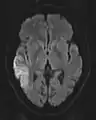

The most common application of conventional DWI (without DTI) is in acute brain ischemia. DWI directly visualizes the ischemic necrosis in cerebral infarction in the form of a cytotoxic edema,[38] appearing as a high DWI signal within minutes of arterial occlusion.[39] With perfusion MRI detecting both the infarcted core and the salvageable penumbra, the latter can be quantified by DWI and perfusion MRI.[40]

DWI showing necrosis (shown as brighter) in a cerebral infarction

An apparent diffusion coefficient (ADC) image, or an ADC map, is an MRI image that more specifically shows diffusion than conventional DWI, by eliminating the T2 weighting that is otherwise inherent to conventional DWI.[24][25] ADC imaging does so by acquiring multiple conventional DWI images with different amounts of DWI weighting, and the change in signal is proportional to the rate of diffusion. Contrary to DWI images, the standard grayscale of ADC images is to represent a smaller magnitude of diffusion as darker.[23]

Cerebral infarction leads to diffusion restriction, and the difference between images with various DWI weighting will therefore be minor, leading to an ADC image with low signal in the infarcted area.[24] A decreased ADC may be detected minutes after a cerebral infarction.[26] The high signal of infarcted tissue on conventional DWI is a result of its partial T2 weighting.[27]